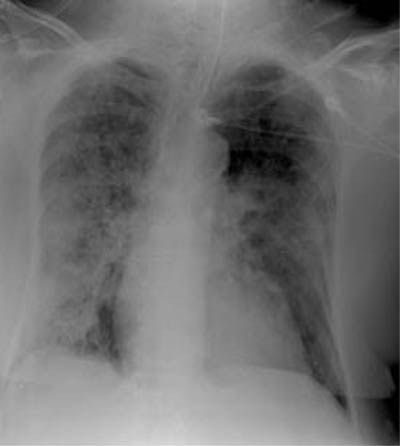

| Radiological signs of SARS include presentation with focal airspace opacity, seen here in the periphery of the right midzone (top image), in approximately 46% of the cases. In 29% of the cases with abnormal radiographs, there were bilateral multifocal opacities (middle image) as well as diffuse opacities, seen here principally in the right lung (bottom image). Images courtesy and copyright of Dr. Narinder Paul, Princess Margaret Hospital, Toronto, ON |

Approximately 25% of the patients are showing normal chest x-rays on admission for SARS, according to Paul. The remaining 75% of patients with abnormal chest x-rays can be divided into two groups.

About 46% of the patients are showing unilateral focal opacities; the remaining 29% are presenting with bilateral multifocal opacities or diffuse opacities. Of these signs, the most worrisome are the diffuse opacities, Paul said, because these patients have shown the highest rate of mortality. Conversations with physicians in SARS-affected areas of China have revealed that these percentages are roughly the same in China, he said.